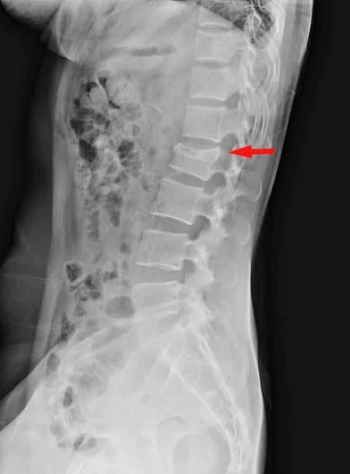

高齢の方の慢性的な腰痛の場合、変形性腰椎症の場合が多いです。基本的にレントゲンを撮って、腰骨の正面と側面、また前かがみや後ろに反らした状態で腰の並びやずれがないかをチェックします。

診断はレントゲンで行います。正面と側面を確認し、つぶれている腰骨がないかチェックします。腰骨がつぶれてなくても安心はできず、不顕性骨折と言ってレントゲンでわからない骨折もあるので、痛みが強い場合はMRIで診断することもあります。